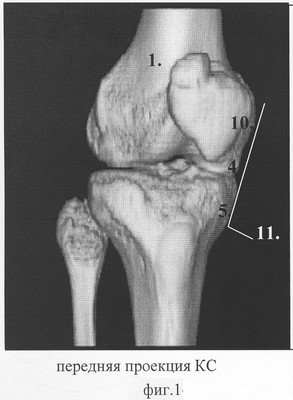

Способ пояснен на фиг.1 – передняя проекция коленного сустава; фиг.2 – боковая проекция коленного сустава; фиг.3 – позиция линейного датчика по линии пересечения медиального мыщелка бедренной кости и медиального мыщелка большеберцовой кости; фиг.4 – позиция указанного датчика, смещенного в область суставной щели в зоне расположения переднего рога внутреннего мениска; фиг.5 – позиция указанного датчика, под углом 30° в зоне расположения тела внутреннего мениска; фиг.6 – эхограмма неизмененного переднего рога и тела внутреннего мениска.

На фиг.1, 2, 3, 4, 5, 6 приняты следующие обозначения:

1 – коленный сустав;

2 – линейный датчик;

3 – внутренняя суставная щель;

4 – дистальный отдел медиального мыщелка бедренной кости коленного сустава;

5 – проксимальный отдел медиального мыщелка большеберцовой кости коленного сустава;

6 – первая позиция, датчик в положении переднего рога внутреннего мениска;

7 – передний рог внутреннего мениска;

8 – вторая позиция, датчик в положении тела внутреннего мениска;

9 – тело внутреннего мениска;

10 – нижний медиальный полюс надколенника;

11 – линия, проведенная между дистальным отделом медиального мыщелка бедренной кости 4 и проксимального отдела медиального мыщелка большеберцовой кости 5 коленного сустава 1.

На фиг.1, 2, 3, 4, 5, 6 на коленный сустав 1 устанавливают линейный датчик 2 в проекции внутренней суставной щели 3, расположенной между дистальным отделом медиального мыщелка бедренной кости 4 коленного сустава 1 и проксимального отдела медиального мыщелка бедренной кости 5 коленного сустава 1. Фиксируют датчик 2 в первой позиции 6 в положении переднего рога 7 внутреннего мениска. Во второй позиции 8 датчик 2 устанавливают в положении тела внутреннего мениска 9 коленного сустава 1 между дистальным отделом медиального мыщелка бедренной кости 4 коленного сустава 1 и нижним медиальным полюсом надколенника 10, соответствующая линии 11.

– линию 11, фиг.1, проведенную между медиальным мыщелком бедренной кости 4 и медиальным мыщелком большеберцовой кости 5.